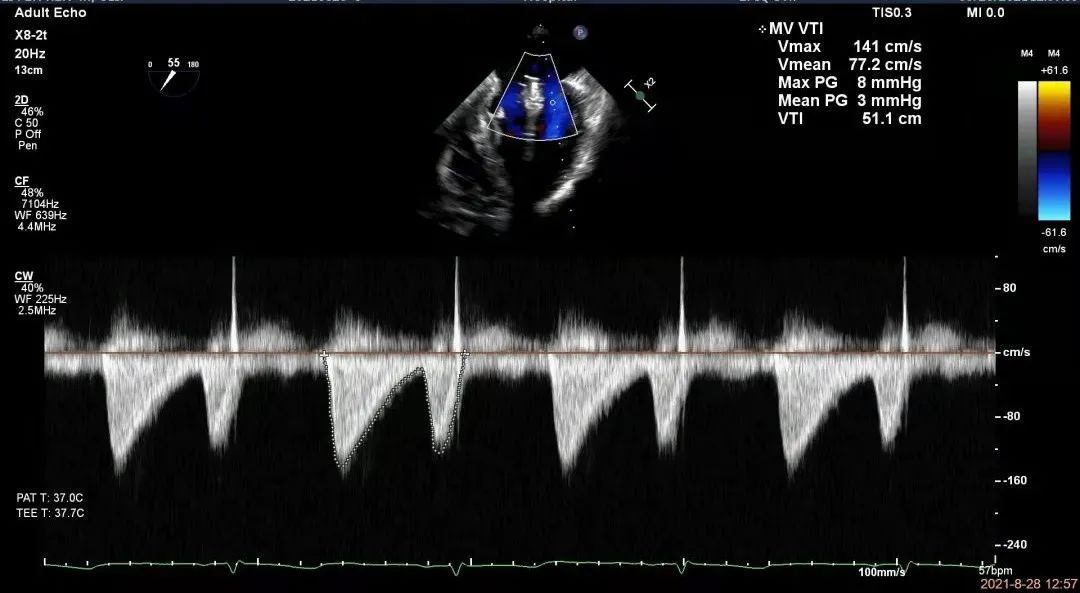

术后超声心动图

术后二尖瓣口血流